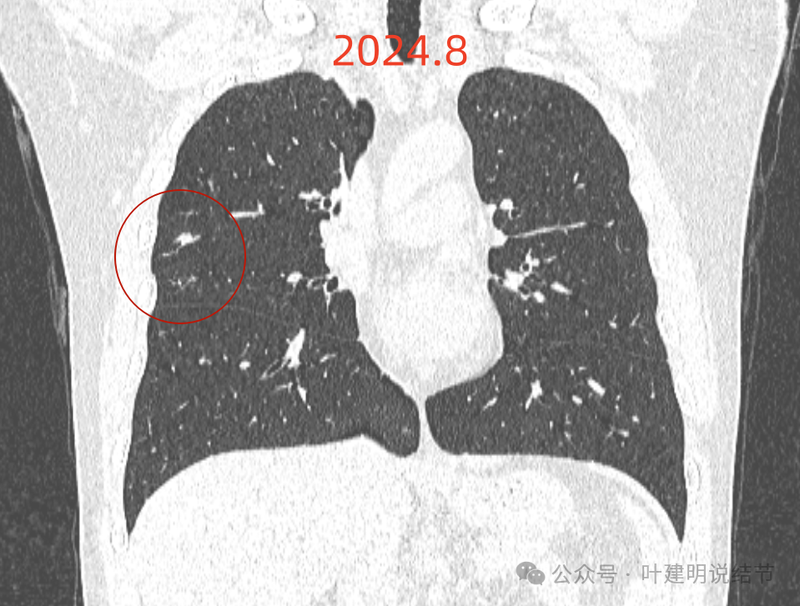

主病灶冠状位见血管紧挨,膨胀性不够。

右上这个结节实性,有血管征的样子,整体轮廓较清,如果从单次来看,是要考虑恶性可能性稍大些的,何况对比2022年时此灶不明显,那是新增的。但我觉得总体上看,倾向良性的一些:1、两肺,尤其是右中叶有多发斑点状实性小结了,较为散在,且对比2022年时无明显进展,说明肺部存在感染性的情况过,他处是遗留有慢性炎或肉芽肿性病变的基础在的,那么主病灶也是同样性质的可能性就增大了;2、冠状位与矢状位看,病灶的瘤肺边界不是很清楚,不像横断面上清楚,说明炎性的可能性是有的;3、实性病灶,但在纵向看,邻近血管并没有受到牵拉影响,没有形成血管弯征,说明收缩力或侵袭性不够。再加上病灶仍小,我的想法是考虑良性可能性大,并建议先4-6个月再复查下,期间也可试试口服莫西沙星消炎10-12天,若更进一步,也可查查结核与隐球菌方面的化验。意见供参考!